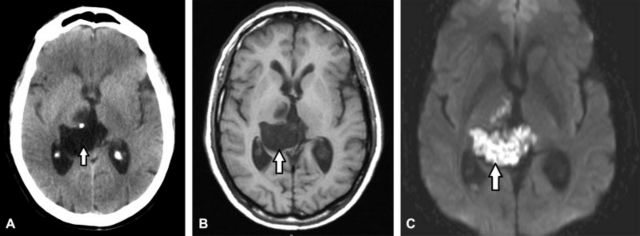

Suelen localizarse (en el 40% de los casos) en el ángulo pontocerebeloso, de ubicación parasagital.3,4,5,8 Tienen origen ectodérmico presentando aspecto perlado, rellenos de agua, queratina, debris y cristales de colesterol.3 Infrecuentemente pueden romperse y originar meningitis química.3,5,6 En TC se expresan como lesiones hipodensas que no realzan con contraste. Raramente calcifican (10–20% de los casos) y si se presentan hiperdensos se debe a saponificación, hemorragia o alto contenido proteico.3,4,5,8 En RM son hipointensos en ponderación T1, hiperintensos en ponderación T2 y pueden presentar sutil realce periférico con gadolinio.3,4,5,8 Característicamente presentan restricción en la secuencia DWI y en la secuencia FLAIR son ligeramente hiperintensos pudiendo diferenciar el contenido líquido de la lesión del LCR (►Fig. 14).3,4,8 Ocasionalmente pueden presentarse quistes "epidermoides blancos" con alto contenido de proteínas siendo hiperdensos en TC e hiperintensos en ponderación T1 e hipointensos en ponderación T2 en RM (►Fig. 15).5 Los diagnósticos diferenciales son:3,4,8

(A-C) Se aprecian en los cortes axial de TC (A), axiales ponderados enT1 (B) y DWI (C) de RM de cerebro, la presencia de una lesión quística localizada a nivel del III ventrículo de ubicación parasagital derecha. En TC es isodensa con el LCR, mientras que en RM se aprecia hipointensa en ponderación T1 con marcada restricción en DWI; comportamiento imagenológico característico de un quiste epidermoide (flechas).

(A-B) RM de cerebro, cortes axiales en impresión a una secuencia FLAIR (A) y DWI (B). Se pone de manifiesto en el ángulo pontocerebeloso derecho una lesión espontáneamente hipertintensa en ponderación T1 que presenta restricción parcial en la secuencia DWI (flechas). La imagen es compatible con "quiste epidermoide blanco."